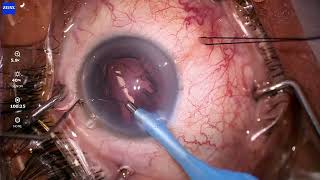

Managing A Small Pupil During Cataract Surgery I Paul Singh, MD video

Managing A Small Pupil During Cataract Surgery - I Paul Singh, MD

Managing A Small Pupil During Cataract Surgery - I Paul Singh, MD Managing a Small Pupil During Cataract Surgery

Managing a Small Pupil During Cataract Surgery MICOR Cataract Extraction Device video - I Paul Singh, MD